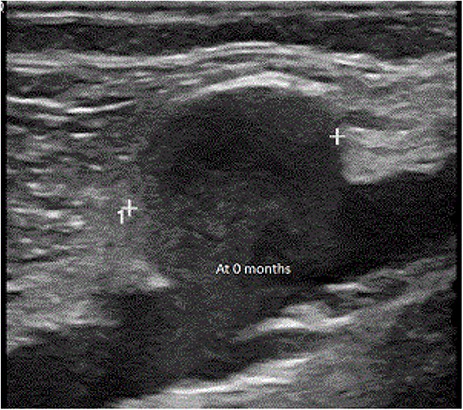

An 81-year-old male with a history of poorly controlled congestive heart failure, chronic obstructive pulmonary disease and atrial fibrillation among other comorbidities was admitted to the hospital for worsening bilateral leg swelling and cellulitis. The patient had an injury to his left medial malleolus 2 weeks prior, which failed outpatient care. During the physical exam, a soft mobile mass was palpated in the right popliteal fossa along with bilateral varicose veins, +1 pitting edema in bilateral lower extremities up to mid-calf. Duplex ultrasound revealed a saccular dilation in the right popliteal vein measuring 2.2 × 1.8 × 2.8 cm, without any evidence of superficial or deep vein thrombosis. After an extended conversation with the patient and his care team, a decision to continue with medical management with close monitoring was made. Follow-up ultrasounds performed at 1, 6 and 12 months show no changes.

An 81-year-old male with a history of poorly controlled congestive heart failure, chronic obstructive pulmonary disease and atrial fibrillation among other comorbidities was admitted to the hospital for worsening bilateral leg swelling and left lower extremity cellulitis. The patient had an injury to his left medial malleolus from an ill-fitting new shoe 2 weeks prior, which had failed outpatient care. During the physical exam, a soft mobile mass was palpated in the right popliteal fossa along with bilateral varicose veins, +1 pitting edema in bilateral lower extremities up to mid-calf. Duplex ultrasound revealed a saccular dilation in the right popliteal vein measuring 2.2 × 1.8 × 2.8 cm (Fig. 1), without any evidence of superficial or deep vein thrombosis (DVT). After an extended conversation with the patient and his care team, a decision to continue with medical management with close monitoring was made. Follow-up ultrasounds performed at 1, 3, 6, 9 and 12 (Fig. 2) months show no changes.